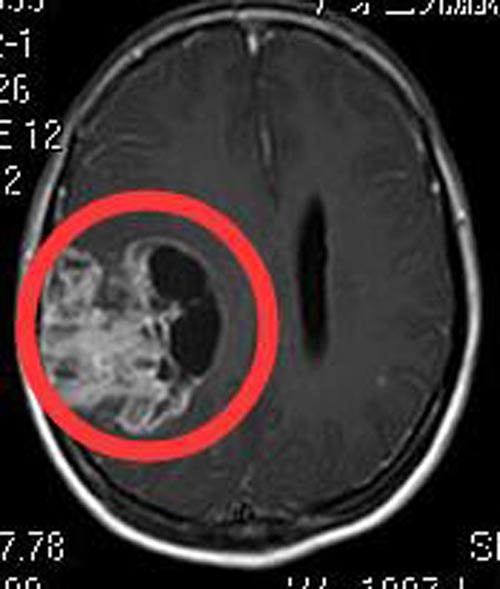

入住广东三九脑科医院综合神经外科时,李女士神志清醒,精神差,急诊行头颅MR检查,显示:右侧颞顶叶占位性病变,大小约6.4cm×6.1cm×5.6cm,考虑偏高级别肿瘤性病变,胶质母细胞瘤或胶质肉瘤可能。

颞叶顶叶占位是跨外侧裂病变,手术难度比较大。由鲁明主任主刀,在唤醒麻醉下行“右颞顶叶占位切除术”,术前导航定位右颞顶叶肿瘤组织,术中再次导航定位,避开肢体运动区及语言区,见灰白色肿瘤组织,质软,超声刀全切除肿瘤,语言、肢体功能配合良好,手术顺利。术后李女士语言、肢体正常。术后病理结果是:胶质母细胞瘤IV级。